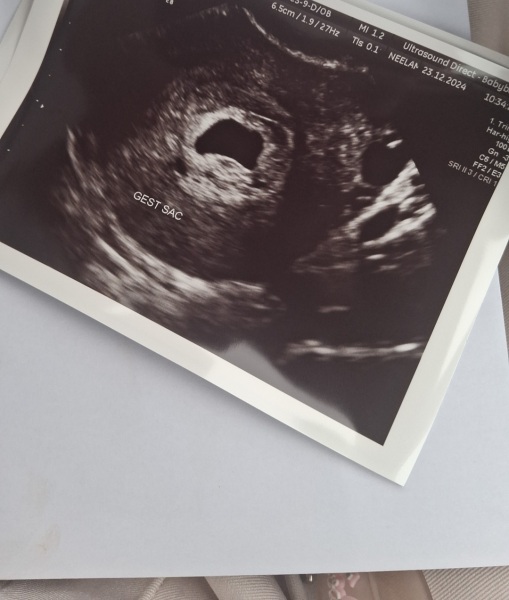

I have had 1 scan at 5w

I thought I was 6w6d

She could not find anything told me to come back only gestational sac visable

4 days later I returned

Irregular shaped sac with irregular lining badly filled fluid and a bleed around the sac still no yolk or fetal.

Slight bleed and pains today

Been told to prepare for the worst as it is not looking good